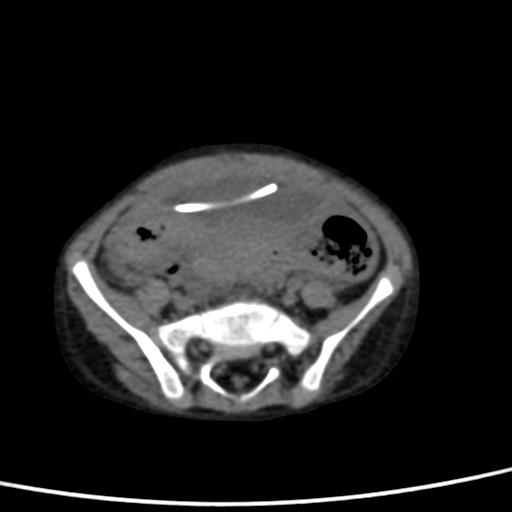

Viene dunque sottoposto ad una TC encefalo che esclude segni di idrocefalo iperteso e a una ecografia e una TC addominale che mostrano la presenza di una formazione cistica plurisettata di circa 7 x 5 x 3 cm all’estremità distale del sistema di derivazione, riferibile a raccolta liquorale (Figura 1).

Figura 1. TC assiale: formazione cistica ovalare in sede sovravescicale contenente l’estremità distale del catetere.